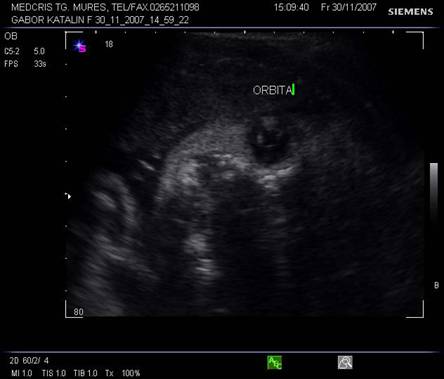

Dupa 13 saptamani in orbita apare si cristalinul in sectiunea parasagitala.

Fig. nr. 160 . Cristalinul hiperecogen, rotund in orbita dreapta .

Planul XIII - indica simultan orbitele si regiunea mandibulara, cristalinul apare ca un inel ecogenic in partea anterioara a orbitelor. Miscarile lente sau rapide ale ochilor pot fi cateodata evidentiate.

Planul XIV - plan oblic pentru orbite si nas.